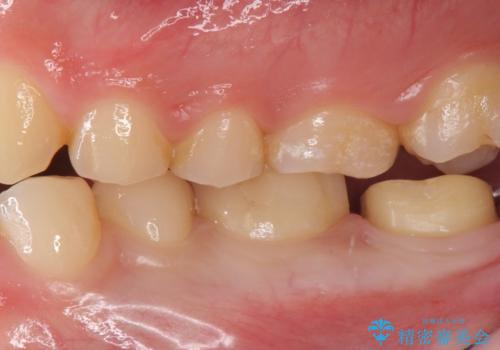

奥歯がしみる 神経を温存する治療

- 奥歯がしみるとのことで来院されました。

検査の結果、古い詰め物の裏側に虫歯ができていること(二次う蝕)が確認されたため、治療していくこととなりました。

虫歯が大きくても、今回のように神経を温存することができる場合があります。